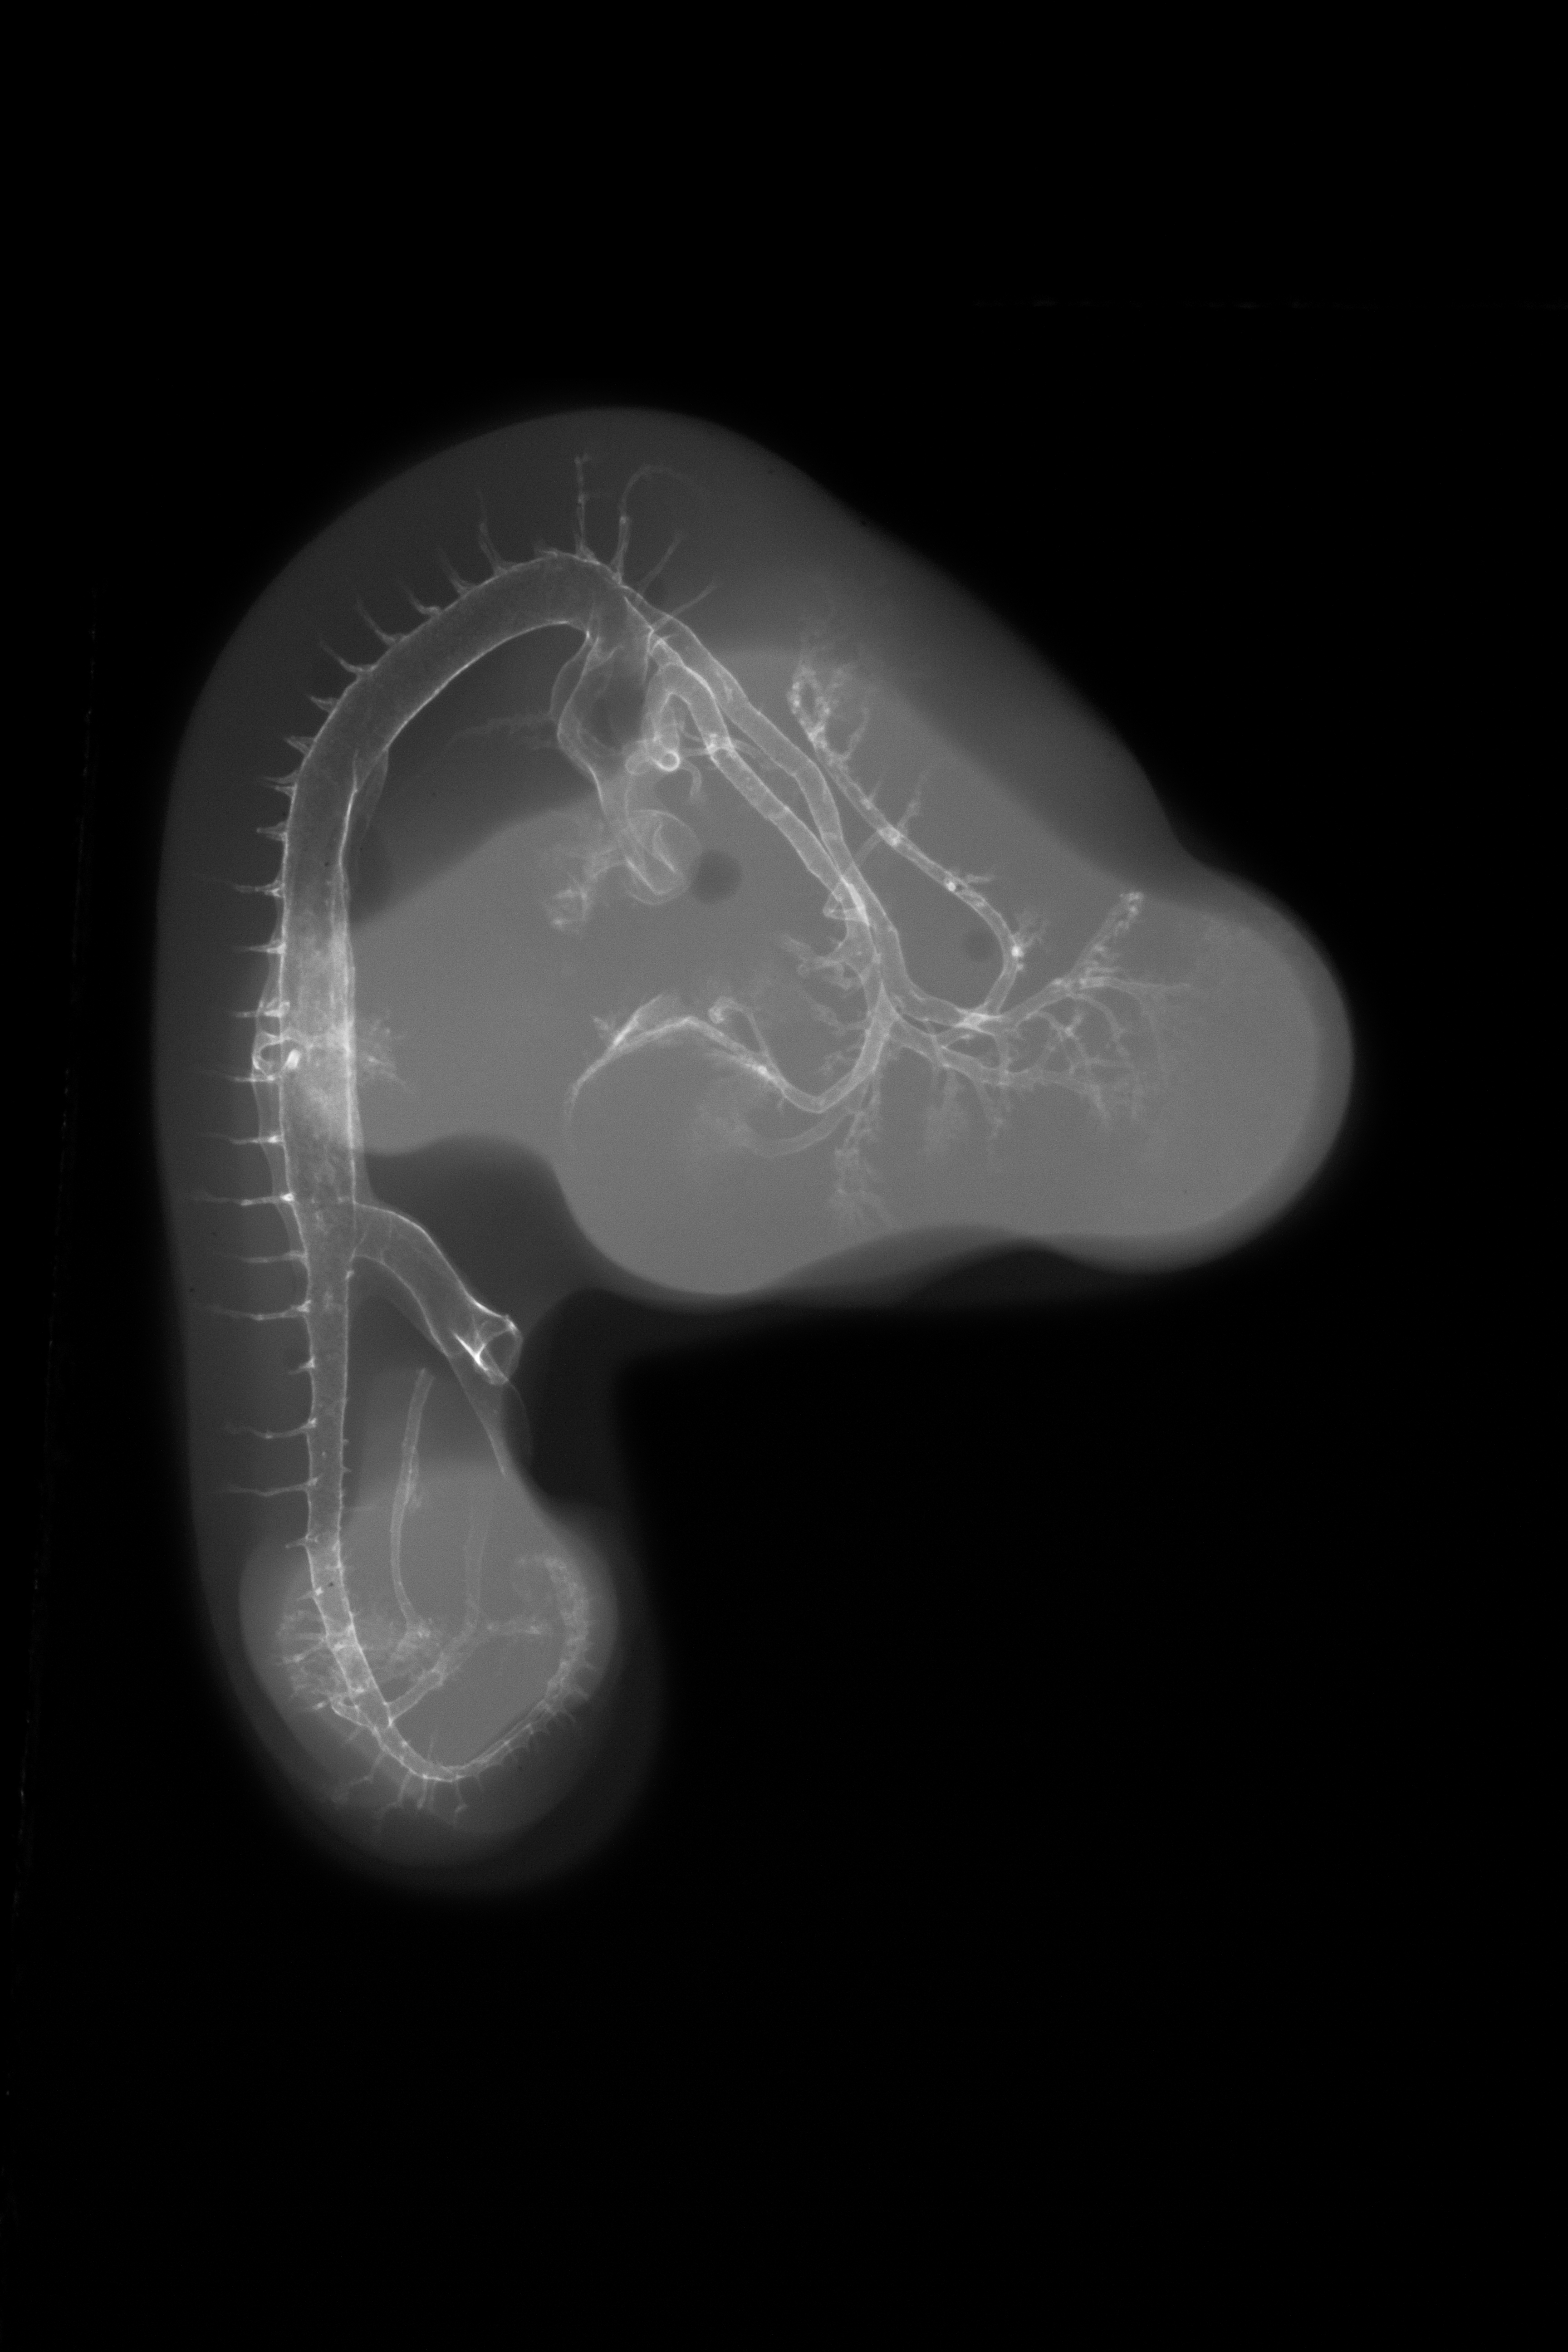

X-Ray Micrographs